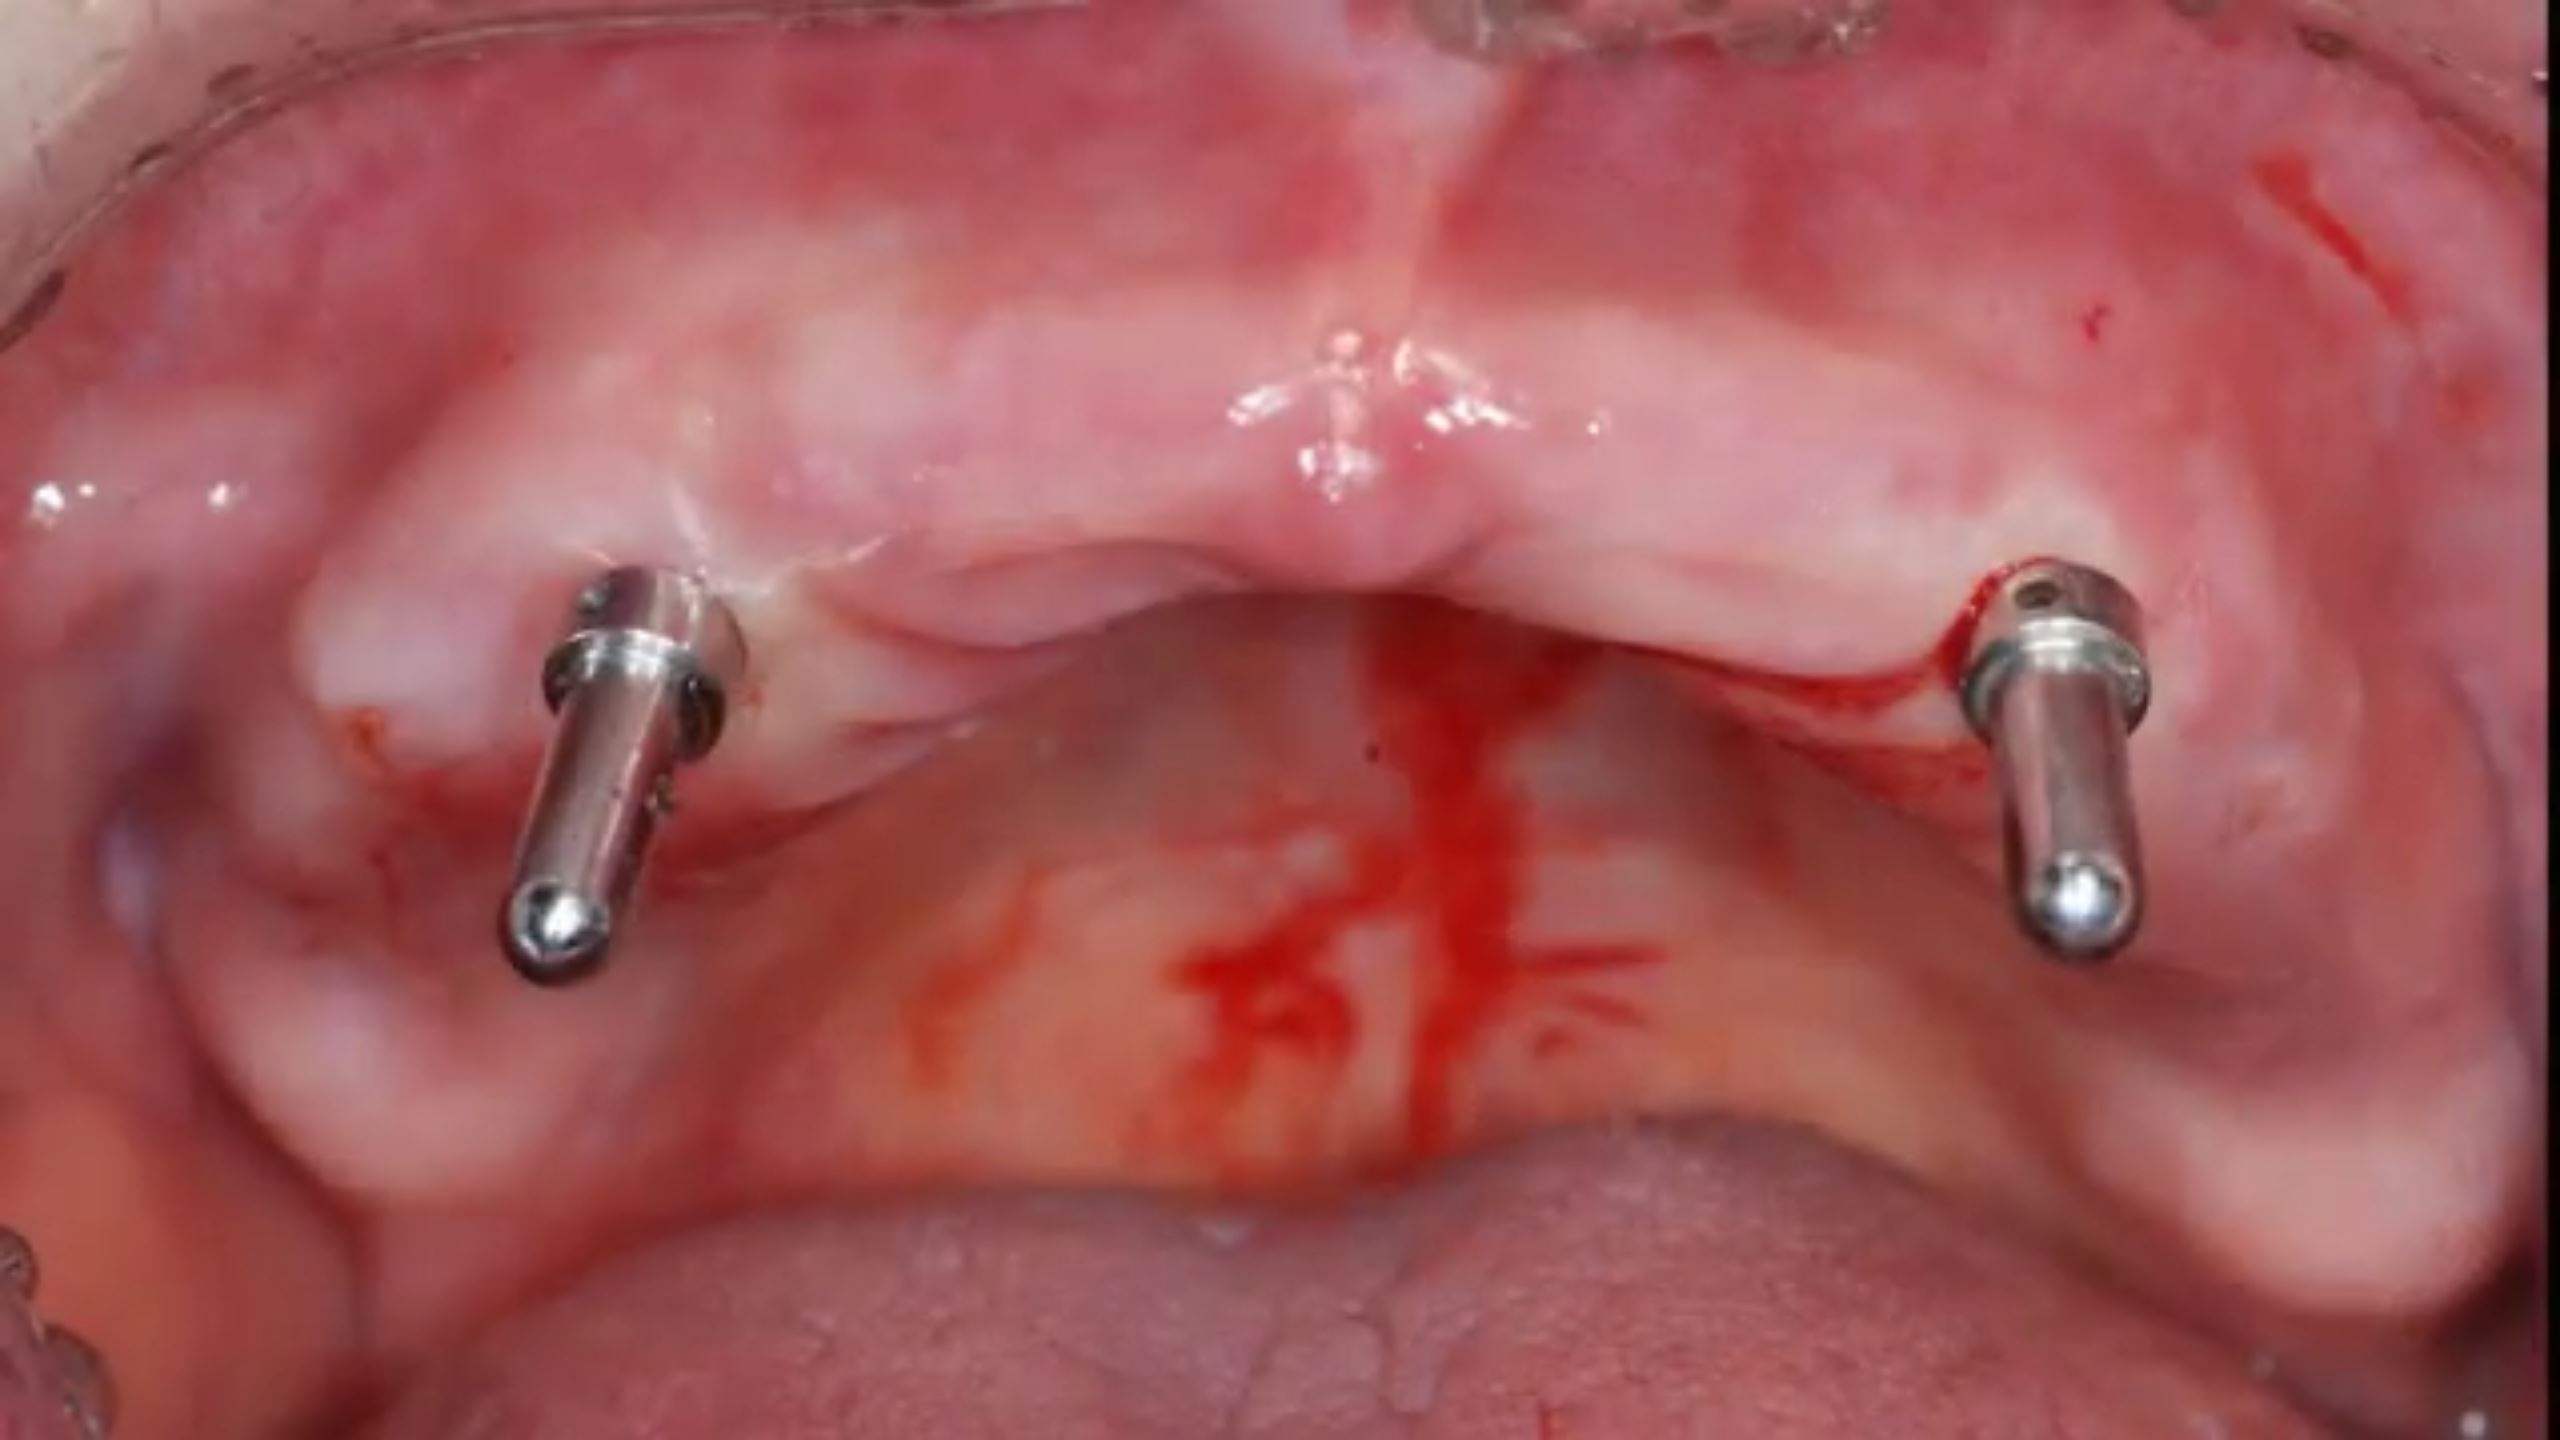

MiNi Clinical Case with Guided Surgery (Live Surgery)

Dr. Jong Cheol Kim,Immediate loading,Digital Guided Surgery,Mandibular Anterior,#31,Guided surgery,Immediate Placement,Flapless,MiNi,R2GATE Guide,MEG-TORQ,MEGA ISQ,Video